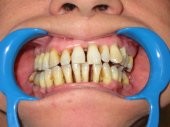

| La Parodontosis o enfermedad periodontal es la fase

final de un fenómeno frecuente en la boca de las personas: la Gingivitis.

Son fases del mismo proceso patológico, que termina, si no media

tratamiento, en la pérdida inevitable de los dientes afectados. Este proceso es consecuencia del llamado TRAUMA OCLUSAL en el que la falta de higiene (placa bacteriana) actúa como agravante. El TRAUMA OCLUSAL es la consecuencia de la pérdida del equilibrio oclusal masticatorio. El dr. Planas es quien mejor ha estudiado y comprendido el trauma oclusal, de tal manera que su conocimiento hace que el tratamiento de los procesos de afectación parodontal resulte efectivo. Eliminando el trauma oclusal cesa la inflamación y el sangrado gingival, se detiene la recesión gingival, desaparece la hipersensibilidad dentinaria, cesa la pérdida de hueso y la movilidad dentaria se reduce. Por todo ello consideramos que el tratamiento de la enfermedad periodontal debe encararse siempre desde el estudio y tratamiento del trauma oclusal, acompañado de los tratamientos necesarios para eliminar la placa bacteriana y el sarro depositado en el parodonto. En la animación se ve el efecto parodontal de una masticación unilateral; la pérdida de soporte óseo en los incisivos con su desplazamiento y apertura de espacios entre dientes. |

Alteraciones de los tejidos parodontales (encía, ligamento y hueso) por problemas funcionales |

Sangrado gingival espontáneo, infecciones

en las encías o movilidad dentaria debidos al desequilibrio oclusal